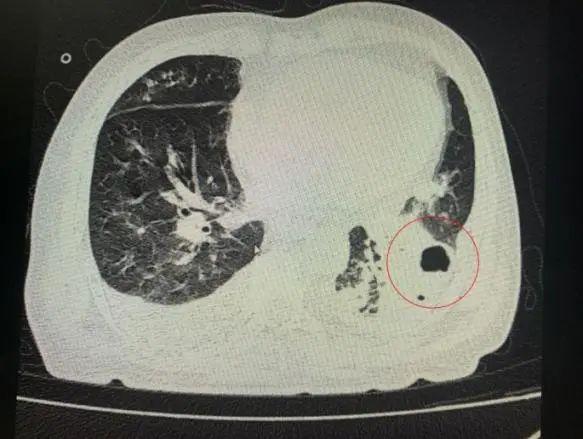

番禺院區(qū)呼吸內(nèi)科何夢(mèng)璋主任接診后,對(duì)鐘叔進(jìn)行詳細(xì)檢查。此時(shí),鐘叔的病情已經(jīng)十分危急,由于不能自主呼吸,他帶上了呼吸機(jī)輔助呼吸調(diào)節(jié)??吹界娛逍仄瑫r(shí),醫(yī)護(hù)人員頭皮也一陣發(fā)麻,胸部CT可見(jiàn)雙肺多發(fā)的炎癥浸潤(rùn)、雙肺多發(fā)空洞。通俗來(lái)說(shuō),鐘叔的肺部已經(jīng)被病原體蠶食,啃出個(gè)大小各異的洞!可怕的是,這種病變對(duì)肺功能的破壞是性、不可恢復(fù)的。根據(jù)鐘叔病史以及胸部CT結(jié)果,終診斷為“吸入性肺膿腫”。

鐘叔的肺部被病原體蠶食,啃出個(gè)大小各異的洞。